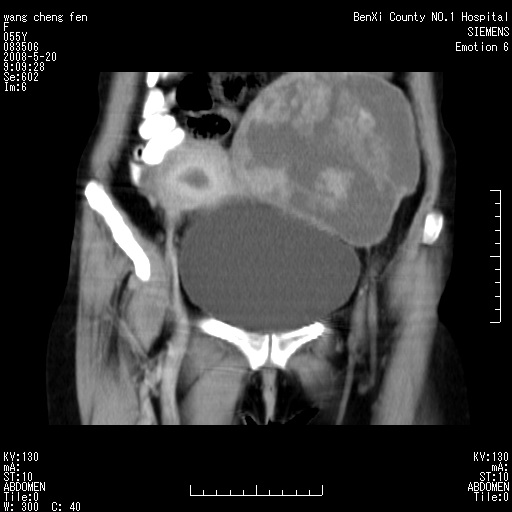

标题: CT3539:盆腔巨大肿瘤增强 [打印本页]

标题: CT3539:盆腔巨大肿瘤增强

女、绝经后阴道流血3个月

宫颈略萎缩、宫颈前唇及阴道前臂可初级结节。

左侧附件区可见一囊性占位,边缘清楚,内可见不规则形软组织影 ce:囊壁及内部可见强化 考虑 卵巢囊腺瘤

左侧附件区巨大囊实性病灶,边缘光整,病灶囊壁较厚,增强示囊壁及实性部分明显强化,强化呈度与宫体实质大致相同,宫腔积液征像,未见盆腔积液等其他异常,考虑左侧卵巢囊腺癌,不除外囊腺瘤及浆膜下肌瘤坏死

左侧附件区巨大囊实性病灶,边缘光整,病灶囊壁较厚,增强示囊壁及实性部分明显强化,强化呈度与宫体实质大致相同,宫腔积液征像,未见盆腔积液等其他异常。绝经后阴道流血3个月,结合病史左侧卵巢囊腺癌首先考虑,宫腔扩大不除外累及。期待结果。